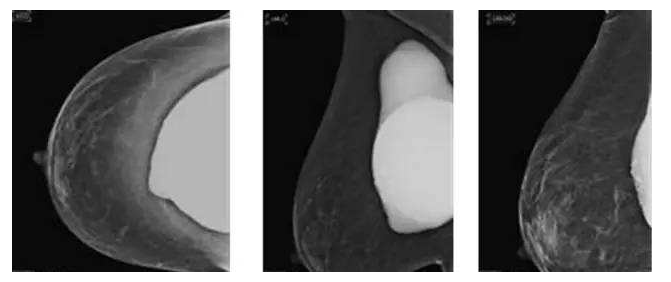

假体隆胸10年后将面临什么样的问题?

假体隆胸手术发展至今已有几十年历程,随之时代的发展,医学的进步,现代隆胸技术在不断升级,假体质量也在不断提高。现代信息的广泛传播,也让受众对于隆胸手术的了解全面化。一台成功的隆胸手术可以维持10年的时间,那么为什么是10年成为了隆胸的关键时期?10年后隆胸的人会面临怎样的问题?

假体老化最常出现的现象,比如囊壁钙化,渗漏,甚至破裂,还会随着人体组织的老化出现下垂问题。

囊壁钙化:硅胶假体在胸部存放时间过长,在硅胶和自身组织包膜之间,就有可能形成钙化沉淀。轻微的钙化不会对人体造成伤害,无需在意。但如果钙化出现较大的结块,而且集中出现在假体周围,便需要做组织取出或手术。

假体渗漏、破裂:囊膜皱褶经反复运动而老化破裂,后期渗漏或破裂,有纤维囊挛缩或急性炎症现象。假体破裂的发生率虽然很低,当假体出现明显的手感变化,形态的变化,那么这个时候就可能出现了假体的破裂,如果出现假体破裂就需要置换假体。

假体松弛下垂

如果出现假体隆胸变软下垂的问题可能是假体置入层次的问题,假体如果是放在胸部腺体下,它会随着自体的胸部往下垂而一起下垂,如果假体放在胸大肌下,那么就会出现腺体往下走,而假体不往下走,就有可能形成四个胸部的情况。